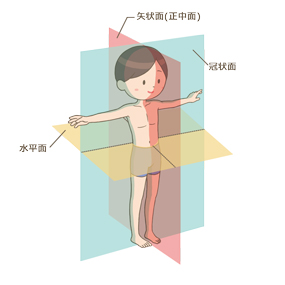

矢状面、冠状面、水平面が分からない? これで完全理解!! 身体の方向をあらわす3つの基準面 矢状面、冠状面、水平面 、本当に理解している?ここって、結構間違えやすい部分だよね。 なので、今回は「矢状面 正中面 」「冠状面」「水平面」のそれぞれの覚え方を。

身体の方向をあらわす3つの基準面 矢状面 正中面 、冠状面、水平面 のイラスト🎨 フリー素材 看護roo! カンゴルー。

矢状面、冠状面、水平面が分からない? これで完全理解!! 身体の方向をあらわす3つの基準面 矢状面、冠状面、水平面 、本当に理解している?ここって、結構間違えやすい部分だよね。 なので、今回は「矢状面 正中面 」「冠状面」「水平面」のそれぞれの覚え方を。

身体の方向をあらわす3つの基準面 矢状面 正中面 、冠状面、水平面 のイラスト🎨 フリー素材 看護roo! カンゴルー。

人体の基準面で矢状面 と 冠状面 がごっちゃになる人へ。 このイラストのイメージがあると記憶に残ります。

矢状面、冠状面、水平面が分からない? これで完全理解!! 身体の方向をあらわす3つの基準面 矢状面、冠状面、水平面 、本当に理解している?ここって、結構間違えやすい部分だよね。 なので、今回は「矢状面 正中面 」「冠状面」「水平面」のそれぞれの覚え方を。

矢状面、冠状面、水平面が分からない? これで完全理解!! 身体の方向をあらわす3つの基準面 矢状面、冠状面、水平面 、本当に理解している?ここって、結構間違えやすい部分だよね。 なので、今回は「矢状面 正中面 」「冠状面」「水平面」のそれぞれの覚え方を。